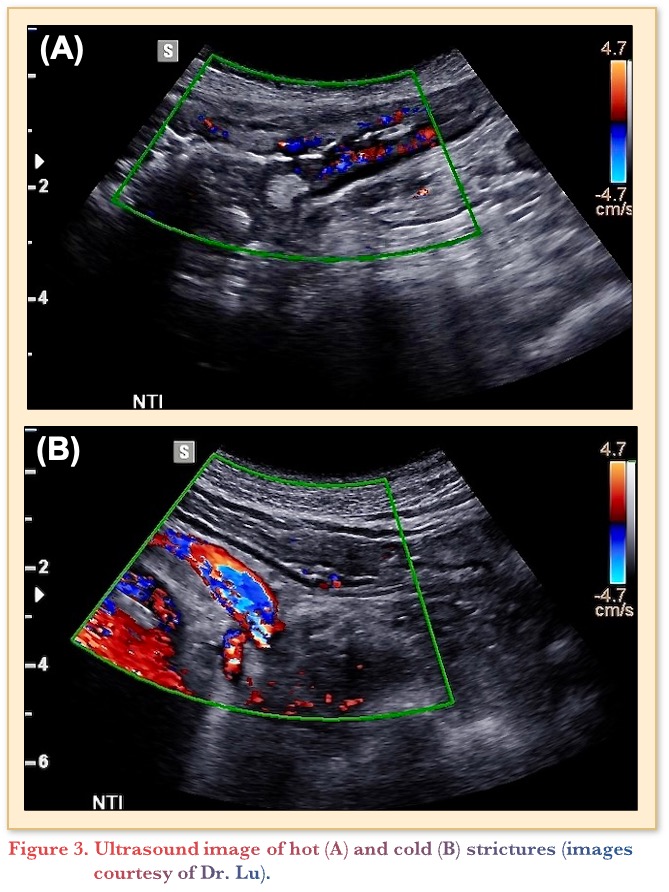

IUS can also be used to discriminate hot and cold strictures. Figure 3 depicts the imaging differences between the two, with a hot stricture (A) and a cold stricture (B). The hot stricture shows ample hyperemia, appearing similar to a string of lights along the bowel wall with prestenotic dilation. The cold stricture is thinner with profound prestenotic dilation covering almost 50% of the screen, with much less signal in the bowel wall itself. This particular patient would benefit from surgery, whereas the patient on the left with the hot stricture could trial additional advanced therapies.